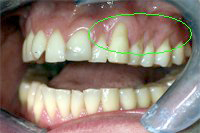

Ein 31 Jahre alter Patient zeigt einen starke Zahnfleisch-Rückgang im Oberkiefer (Abb. 1 und 3) und wir beschliessen, diese Rezessionen zu behandeln.

Der Erfolg der Behandlung ist deutlich in den Abb. 2 und 4 zu sehen. Sehr augenfällig konnte die Situation um den Eckzahn im linken Oberkiefer verbessert werden (vergleiche dazu Abb. 3 vorher und Abb. 4 nachher).